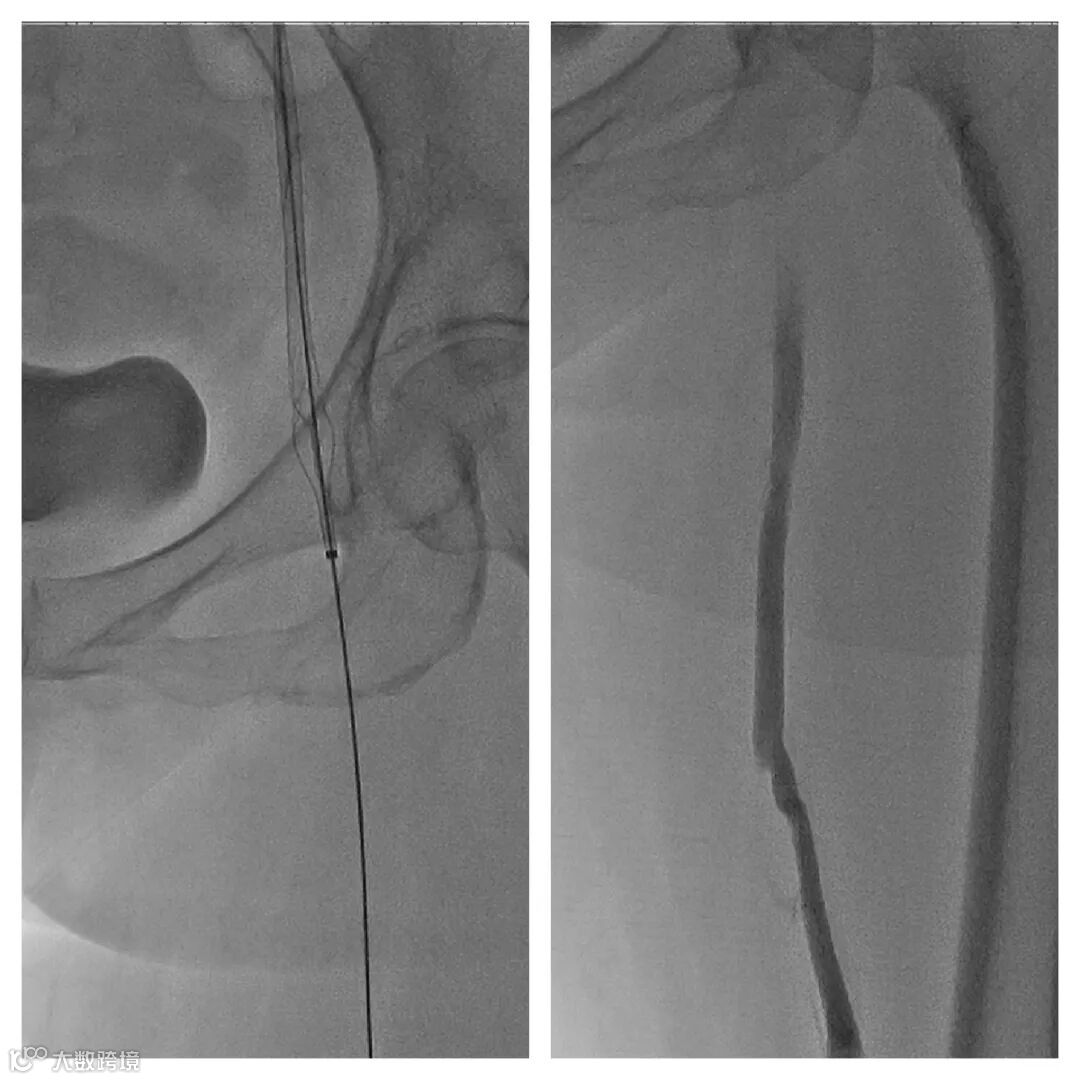

4. 送入腾复Tendfast®外周静脉取栓支架,左股静脉拉栓1次,造影显示:左股静脉血流通畅。

5. 左髂静脉血栓负荷较重,通过左髂总静脉后,给予6mm*150mm球囊扩张。

6. 引入Tendfast®外周静脉取栓支架,从左侧髂静脉拉栓2次,造影显示血流恢复通畅。